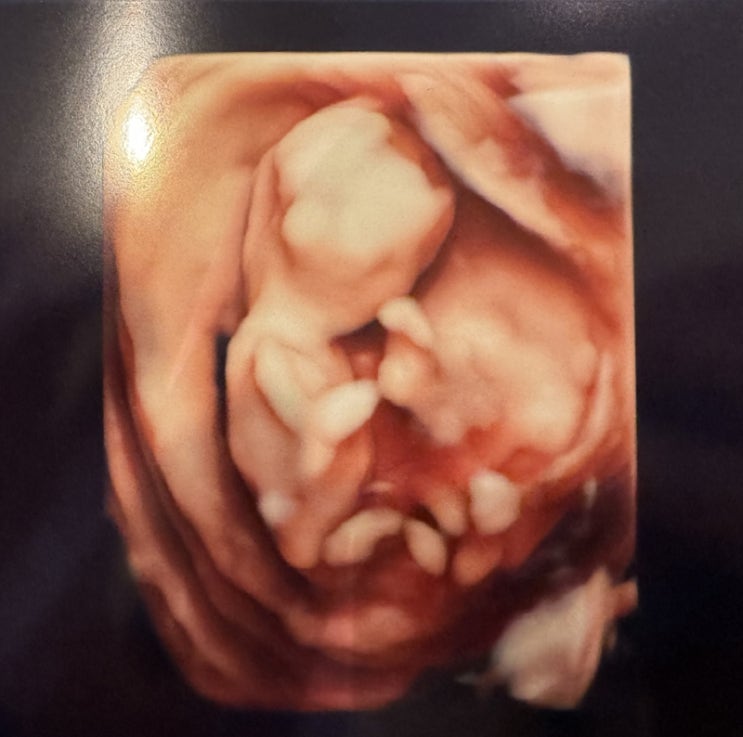

히빵이 30주 일기 - 안양 봄빛 4D 입체초음파 촬영하고 왔어요

히빵이 애미의 30주 일기 4D 입체초음파 촬영 ♥ 드디어 기다리던 입체 초음파를 하고 왔어요! 임신을 알...